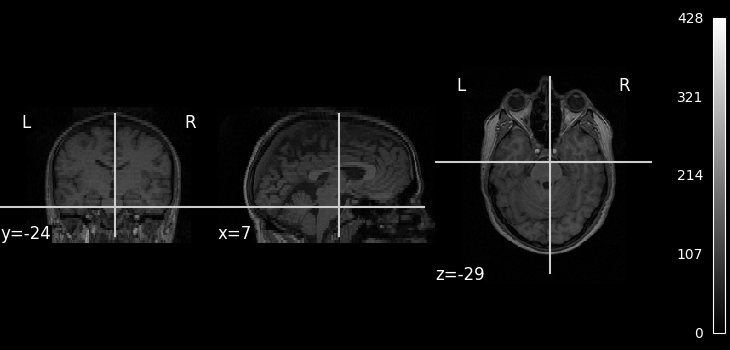

We can display the first functional image and the subject’s anatomy:

from nilearn.plotting import plot_anat, plot_img, plot_stat_map

plot_img(subject_data.func[0], colorbar=True, cbar_tick_format="%i")

plot_anat(subject_data.anat, colorbar=True, cbar_tick_format="%i")